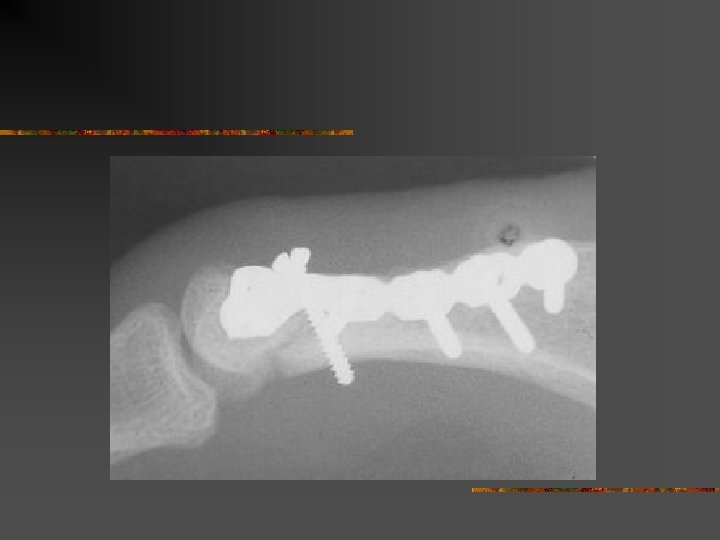

Homme de 61 ans. Traumatisme index droit par pétard à taupe. Dévascularisation. Revascularisation par pontage veineux